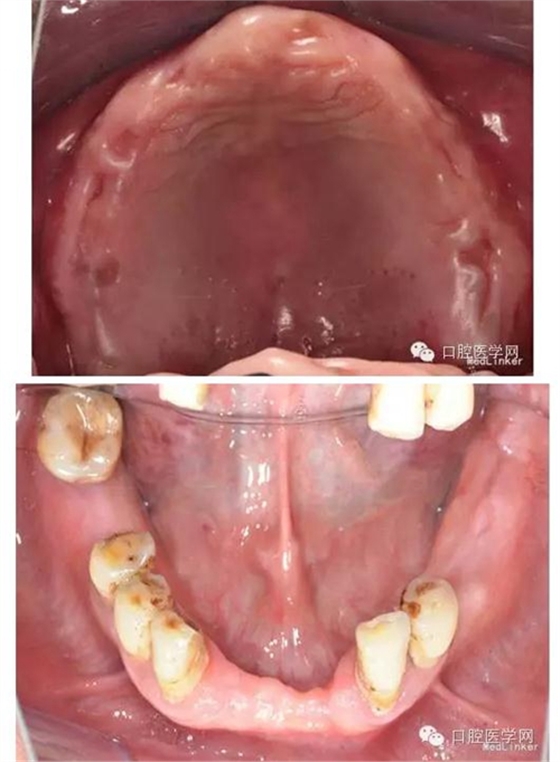

2、口內(nèi)檢查:口腔衛(wèi)生較差,PIL=2,CI=2;黏膜紅潤無潰瘍,厚度及移動度正常;唇頰系帶附著正常、腭穹窿形態(tài)正常;唾液分泌正常。上頜無牙頜,牙槽嵴較豐滿,右上術(shù)區(qū)愈合良好,無尖銳骨棱、骨刺,未見明顯倒凹。#35-#38、#32-#42及#46、#48缺失,牙槽嵴無明顯吸收;#33#43伸長約2mm,叩(-),松(-);#46近中傾斜,叩(-),松Ⅰ度,#34頰側(cè)頸部楔狀缺損,未探及敏感,叩(-),松Ⅰ度;#33#34 及#43-#45,牙齦萎縮,he面嚴重磨耗,叩(-),松(-)。